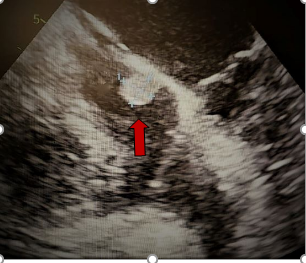

Το θηλοειδές ινοελάστωμα

Το θηλώδες ή θηλοειδές ινοελάστωμα είναι ένας καλοήθης όγκος που εμφανίζεται κυρίως επάνω σε καρδιακές βαλβίδες. Είναι ο πιο συνηθισμένος όγκος των καρδιακών βαλβίδων. Η μέση ηλικία των ασθενών είναι 60 έτη. Η διάμετρος του είναι συχνά <1 εκατοστό, αλλά μπορεί να φτάσει 1-2 εκατοστά, έχει ένα μικρό μίσχο και ένα σχήμα που μοιάζει με θαλάσσια ανεμώνη. Στην ηχοκαρδιογραφία, αυτοί οι καλοήθεις όγκοι έχουν μικρό μέγεθος, με ανεξάρτητη κίνηση και προσάρτηση σε μια ενδοκαρδιακή επιφάνεια (συνήθως μιας βαλβίδας) μέσω ενός κεντρικού μίσχου. Ο όγκος έχει συνήθως στην επιφάνειά του μικρές δακτυλοειδείς προσεκβολές και το περιγράμμά του εμφανίζει μία λεπτή τρομώδη κίνηση λόγω κραδασμών στη διαχωριστική επιφάνεια όγκου-αίματος. Η πιο συνηθισμένη θέση είναι η αορτική βαλβίδα, ακολουθούμενη από τη μιτροειδή βαλβίδα και σπάνια τις δεξιές βαλβίδες ή ακόμα και το τοιχωματικό, μη βαλβιδικό ενδοκάρδιο. Τα ινοελαστώματα μπορούν να προκαλέσουν βαλβιδική ανεπάρκεια και θρομβοεμβολικές επιπλοκές. Οι θρομβοεμβολικές επιπλοκές μπορεί να εκδηλωθούν ως παροδικό ισχαιμικό, ή εγκατεστημένο εγκεφαλικό επεισόδιο, έμφραγμα του μυοκαρδίου, αιφνίδιος θάνατος, συγκοπή, τύφλωση ή πνευμονική εμβολή. Εάν ο όγκος βρίσκεται στην αρτηριακή πλευρά της αορτικής βαλβίδας, μπορεί να προκαλέσει στεφανιαία απόφραξη. Η χειρουργική εκτομή του όγκου είναι θεραπευτική και αποτελεί λογική απόφαση σε συμπτωματικούς ασθενείς ή όταν ο όγκος έχει διαγνωσθεί σε προεγχειρητικό υπερηχογράφημα καρδιάς σε ασθενή που πρόκειται να υποβληθεί σε καρδιοχειρουργική επέμβαση για άλλο λόγο.